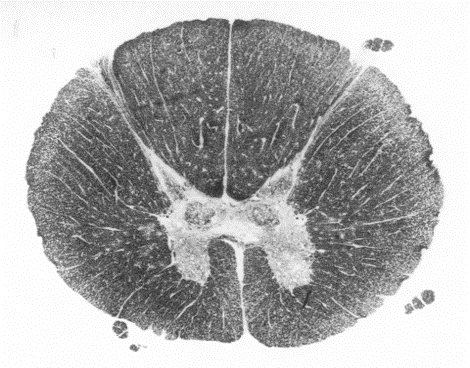

18

spinal cord. dorsal horn grey matter at the top half and ventral at the bottom

A

cervical region of spinal cord

thoracic region of the spinal cord

lumbar region of the spinal cord

24

sacral region of the spinal cord